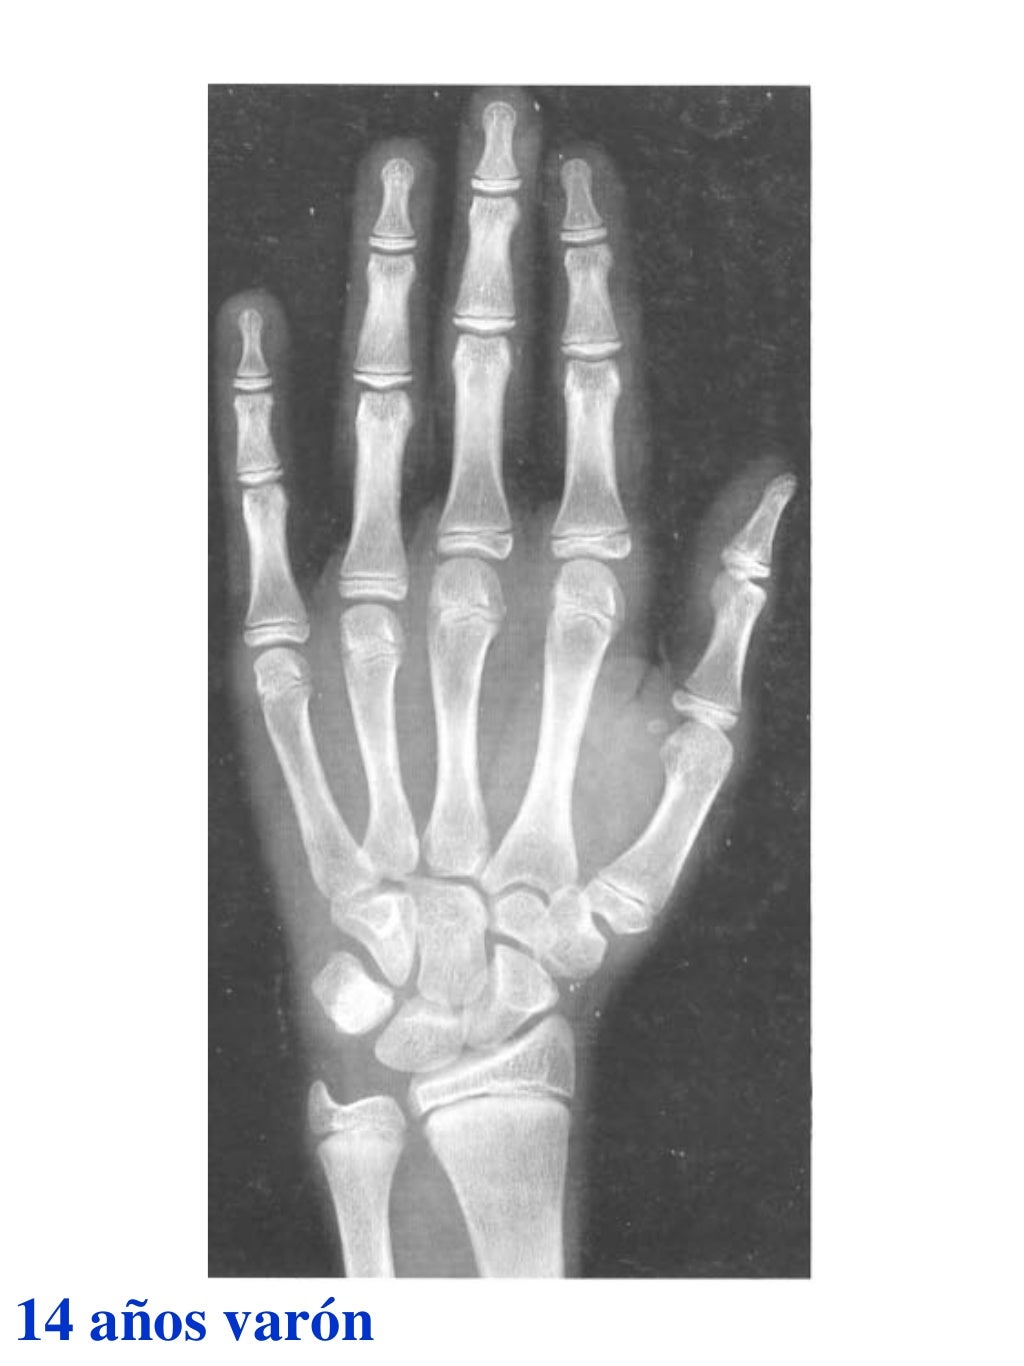

Tablas De Greulich Y Pyle . Scribd is the world's largest social reading and publishing site. This systematic review summarizes the. The radiographic atlas of skeletal development of the hand and wrist by ww greulich and si pyle is a classic radiological. The standards established by greulich and pyle, undoubtedly the most popular method, consist of two series of standard plates. The greulich and pyle method is one of the two main ways to assess the bone age of children. El documento lista las edades. Both main methods of bone age. 153 recomendaciones • 616,869 vistas. Atlas greulich y pyle | pdf | descarga gratuita. The greulich and pyle atlas is used to estimate the age of children and adolescents.

Tablas De Greulich Y Pyle The standards established by greulich and pyle, undoubtedly the most popular method, consist of two series of standard plates. The standards established by greulich and pyle, undoubtedly the most popular method, consist of two series of standard plates. El documento lista las edades. This systematic review summarizes the. The greulich and pyle method is one of the two main ways to assess the bone age of children. Both main methods of bone age. Scribd is the world's largest social reading and publishing site. 153 recomendaciones • 616,869 vistas. Atlas greulich y pyle | pdf | descarga gratuita. The greulich and pyle atlas is used to estimate the age of children and adolescents. The radiographic atlas of skeletal development of the hand and wrist by ww greulich and si pyle is a classic radiological.